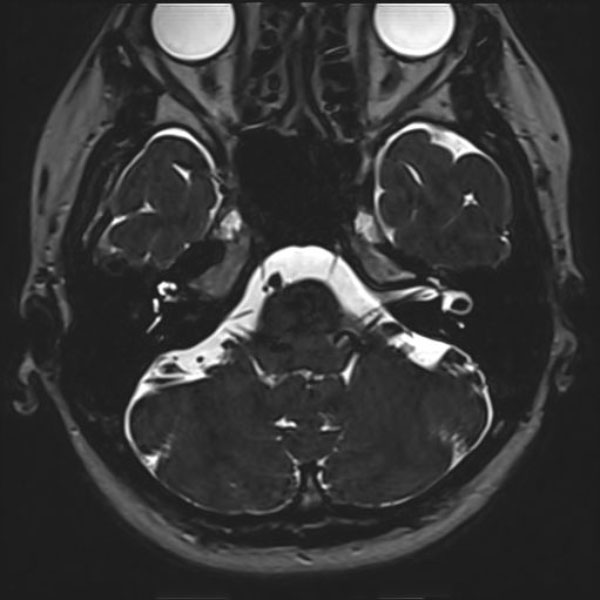

581

大阪府の病院

'26年3月

40代

左顔面痙攣

手術前

減圧前

減圧後

術後血管撮影